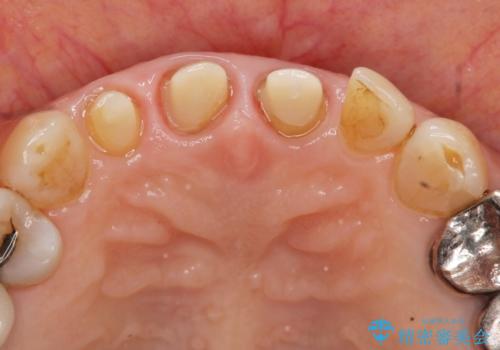

結婚式に合わせて根管治療からのやりかえを短期集中治療で計4回で終える計画を立てます。

- 40万円(仮歯・ファイバーコア・ジルコニアクラウン×3)費用は治療当時の料金となります

セラミック治療は外から見えるのはクラウンの色味・形態、歯肉の状態のみですが、X線撮影において現れるクラウンと歯牙の適合や、ファイバーコアの精度・根管充填の密度に、より長い予後を達成するための要素が含まれると考えます。